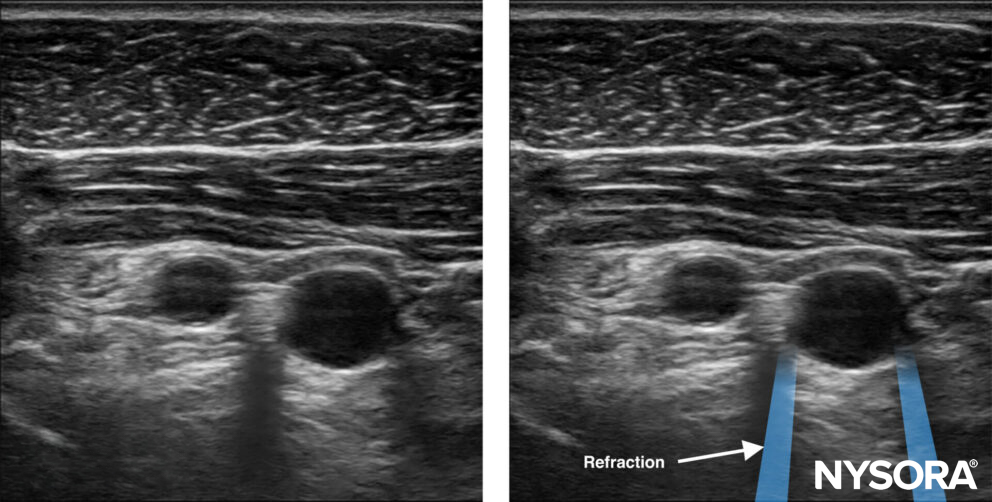

Refraction

Refraction is the appearance of the sound wave being bent when the ultrasound beam obliquely crosses an interface with tissues with different densities and, thus, different propagation speeds. It may result in an acoustic shadow at the interface boundary or a duplication artifact.

Refraction artifacts occur at the edges of vessels.

Illustration (a) shows how sound beam refraction results in a duplication artifact. (b) is a transverse midline view of the upper abdomen showing duplication of the aorta (A) secondary to rectus muscle refraction. The ultrasound figure was published in Atlas of Ultrasound-guided Procedures in Interventional Pain Management, Copyright Elsevier (2004).